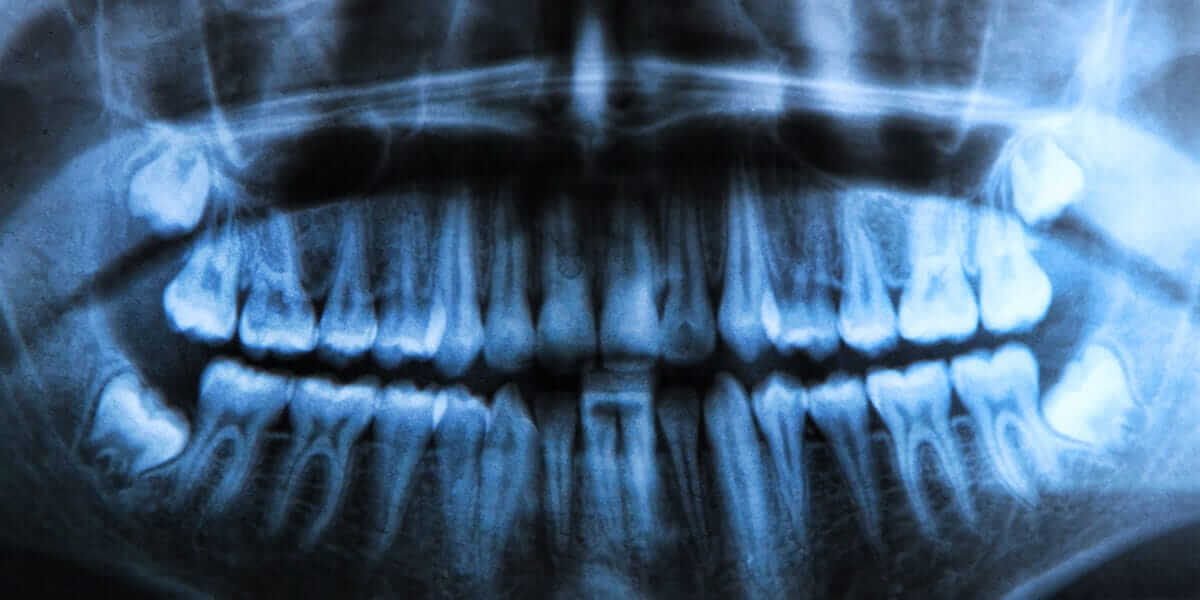

جراحی دندان عقل یکی از رایجترین عملهای دندانپزشکی است که به منظور حذف دندانهای عقل انجام میشود. دندان عقل چیه؟ این دندانها معمولاً در سنین 17 تا 25 سالگی رشد میکنند و در آخرین قسمت فک بالا و پایین قرار دارند. در بسیاری از موارد، دندان عقل به دلیل عدم فضای کافی برای رشد یا رشد نادرست، به مشکلاتی مانند درد، التهاب یا عفونت منجر میشود. برای رفع این مشکلات، جراحی دندان عقل ضروری است. جراح دندان عقل با استفاده از تکنیکهای دقیق و تجهیزات پیشرفته، دندانهای عقل را از فک بیمار خارج کرده و از بروز عوارض جدی جلوگیری میکند. این جراحی معمولاً تحت بیحسی موضعی انجام میشود و در بیشتر موارد، بیماران بعد از عمل به سرعت بهبود مییابند. برای انجام جراحی دندان عقل، مراجعه به یک جراح دندان عقل با تجربه و متخصص ضروری است.

جراحی دندان عقل برای افرادی که دندان عقل آنها به درستی رشد نکرده و باعث ایجاد مشکلاتی مانند درد، عفونت، یا آسیب به دندانهای مجاور میشود، ضروری است. افرادی که دندان عقل آنها به صورت نهفته یا نیمهنهفته در فک باقی میماند، ممکن است با مشکلاتی مانند التهاب لثه، تجمع باکتریها و پوسیدگی مواجه شوند. همچنین کسانی که فضای کافی برای رشد دندان عقل ندارند یا دندانهایشان در موقعیتی نامناسب قرار گرفتهاند، باید برای جراحی دندان عقل اقدام کنند. این جراحی میتواند از مشکلات جدیتری مانند آسیب به ریشه دندانهای مجاور، عفونتهای شدید و دردهای مداوم جلوگیری کند. مشاوره با متخصص کشیدن دندان عقل میتواند به تشخیص دقیق نیاز به جراحی کمک کند.